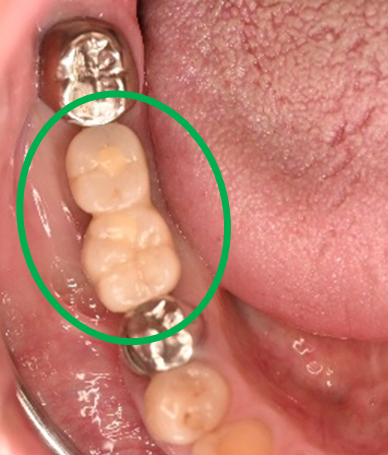

男性 Kさん 60代 (インプラント)

主訴

右下に1本の義歯を入れていたが、インプラントにしたい。

治療内容

インプラントを埋入しました。

所感

2026年2月9日にインプラント埋入手術をし、5月1日に最終的な被せ物を入れました。ブリッジや義歯は、歯がないところに掛かる力を、他の歯が支えることになります。インプラントは、他の歯に負担をかけることはありません。一本欠損になってしまったときは、1本だけインプラントを入れて、他の歯を護り、それ以上歯を失わないことが大切になります。

インプラント:¥363,000(税込)

Before

After